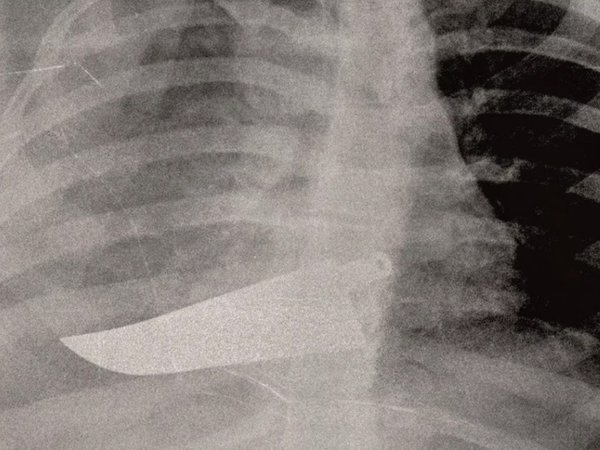

Με την ευκαιρία αυτή, στο μιλανέζικο νοσοκομείο Σαν Κάρλο και με πρωτοβουλία της ιατρού Μαρία Γκράτσια Βανταντόρι, 59 ετών, χειρουργού επί 26 χρόνια εκεί, γίνεται έκθεση ακτινογραφιών γυναικών οι οποίες προσήλθαν στο νοσοκομείο κατόπιν σοβαρού τραυματισμού τους.

Σπασμένη Κνήμη

Η ιατρός περιγράφει τα συνήθη: «Σπασμένα οστά σε μύτη, χέρια, πόδια, πληγές από μαχαιριές, εγκαύματα, μελανιές και άλλα σημάδια στραγγαλισμού». Αλλά και τα ασυνήθη: «Μέχρι και με ένα μαχαίρι καρφωμένο στην πλάτη της μας ήρθε μια γυναίκα».

Έτσι η Βανταντόρι αποφάσισε να εκθέσει «εικόνες από έναν αόρατο πόλεμο που διεξάγεται καθημερινώς πίσω από τους τοίχους των σπιτιών», δηλαδή τις ανώνυμες ακτινογραφίες οι οποίες δείχνουν τα βασανιστήρια που υπέστησαν οι γυναίκες «από συζύγους, πρώην συζύγους, συντρόφους».